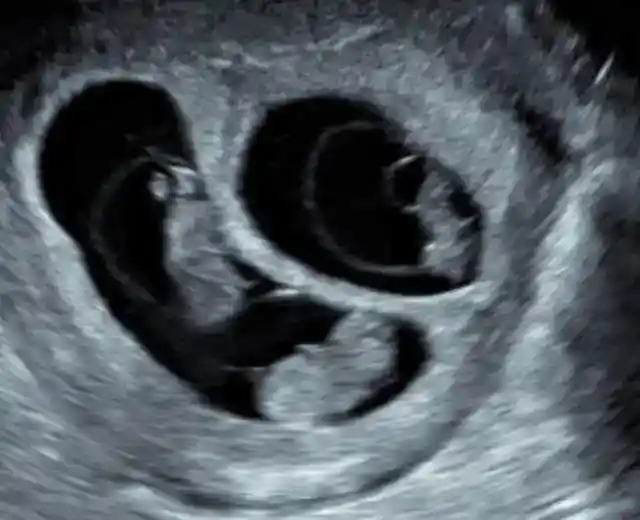

It was due to the fact that she was not only expecting one baby.

Angie was pregnant with three. Just imagine she needed to carry three babies at once!

It was certainly right for the doctors to want to ensure everything was fine.

The pregnancy was quite unique for Angie. However, as you may have already guessed, after learning that they were having triplets, Angie and Gino could not be more ecstatic.

As for two of the babies in Angie’s womb, they were sharing one placenta.

The fact that there was only one placenta for two babies was not really a major problem, but it certainly had its disadvantages for the babies.

The size of one baby was going to be hampered and it wouldn’t get to be the same size as the other babies in Angie’s belly. Nevertheless, there were a lot of other possible complications which were listed, which this problem paled in comparison with.